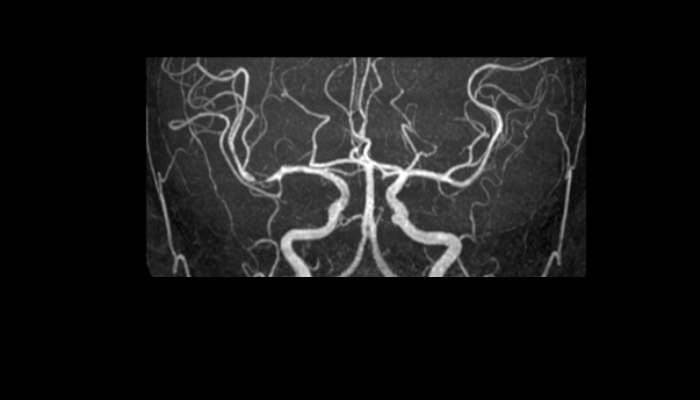

頭部MRI画像 頭部MRI脳腫瘍や脳梗塞、認知症など脳の病気を詳細に評価します。 MRA画像 頭部MRA造影剤を使わずに脳の動脈を描出します。動脈瘤や狭窄を検索します。 脊椎MRI画像 脊椎MRI椎間板ヘルニアや脊柱管狭窄症など脊椎や脊髄の疾患を評価します。 腹部MRI画像 上腹部MRI・MRCP肝臓・胆のう・膵臓・腎臓などの上腹部の重要臓器を詳細に評価します。 乳房MRI画像 乳腺MRIマンモグラフィや超音波と併せて、乳がんを検索や病変の範囲を評価します。 前立腺MRI画像 前立腺MRI前立腺がんを検索します。PSA高値の方はまず前立腺MRIをお勧めします。 子宮・卵巣MRI画像 子宮・卵巣子宮筋腫や子宮体癌、卵巣腫瘍など女性特有の病気を評価します。 膝関節MRI画像 膝関節膝関節の骨や靭帯、半月板を評価します。靭帯断裂や半月板損傷などレントゲンでは評価できない構造も診断できます。 肩関節MRI画像 肩関節肩関節の骨や腱、靭帯を評価します。腱板断裂や腱の断裂などレントゲンでは評価できない構造も診断できます。 心臓MRA 心臓MRA狭心症、心筋梗塞の原因となる冠動脈の狭窄を評価します。造影剤を使用せず、撮影可能です。 DWIBS画像 DWIBS全身のがんを広く検索します。リンパ節や転移の評価にも優れます。